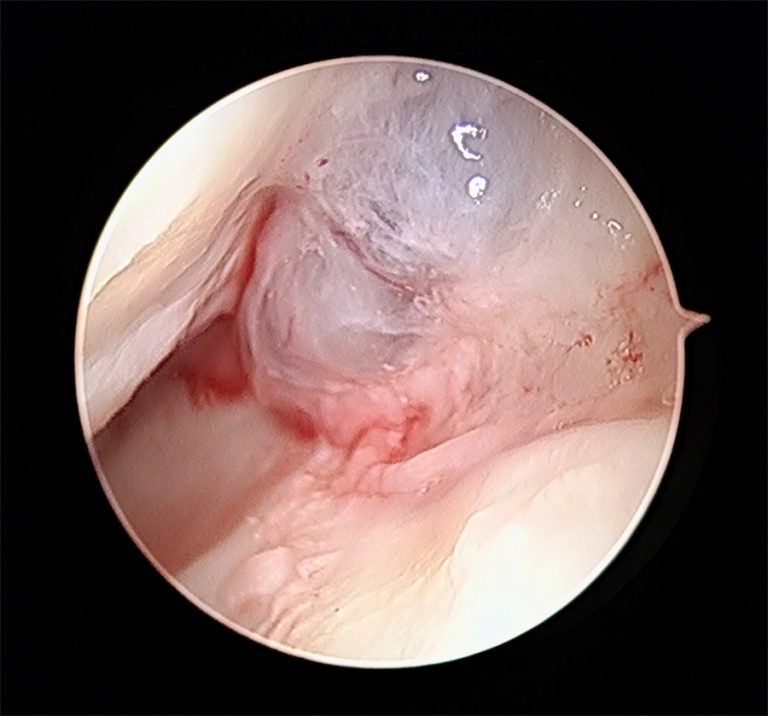

A cirurgia é um procedimento feito em ambulatório e dura cerca de 20 a 30 minutos, sendo geralmente feita de forma minimamente invasiva através de artroscopia do punho.

Aspecto intra-articular de um volumoso quisto sinovial, visto por artroscopia